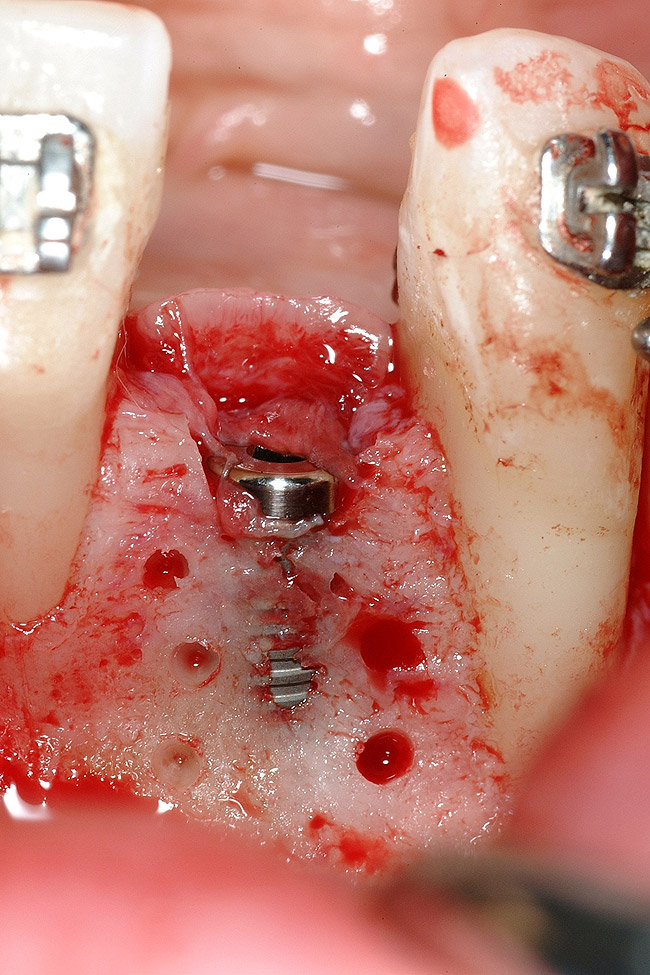

Figure 18  Implant placement with resulting facial dehiscence. Cortical perforations placed to promote angiogenesis.

Figure 18

Figure 19  Mineralized freeze-dried bone allograft hydrated with platelet-derived growth factor covering root dehiscences and implant dehiscence.

Figure 19

Following the first goal of orthodontia—moving tooth No. 22 to a proper functional and anatomical position—a periodontal reevaluation was performed, demonstrating an improvement in short- and long-term tooth prognosis. At this time, the decision was made to abort continual extrusion of teeth Nos. 21 and 22, although some attachment level discrepancy remained between Nos. 21 and 22 (Figure 14). Implant diagnostics ensued and included mounted study models and a diagnostic wax-up. A scanning appliance was created to demonstrate the desired prosthetic outcome requirements, and the patient was referred for computed tomography (CT) scans. CT scan assessment demonstrated successful orthodontically directed GBR to allow implant placement (Figure 15 through Figure 16). Only minor GBR therapy would be needed and could be accomplished simultaneously with implant installation. Guided implant placement occurred, using an open flap approach (Figure 17). During surgery, root dehiscences were noted on teeth Nos. 21, 22, 24, and 25, as well as the anticipated dehiscence following implant placement at No. 23 (Figure 18). A positioning reference (index) was secured after implant placement to facilitate a provisional prosthesis at stage II surgery. Cortical perforations then were placed adjacent to the implant to encourage angiogenesis (Figure 18), and mineralized freeze-dried bone allograft enhanced with platelet-derived growth factor was placed over the dehiscences for purposes of guided tissue regeneration and GBR (Figure 19). A highly resorbable collagen membrane was placed to stabilize the allograft. The flap was coronally repositioned, and primary-intention wound healing was achieved (Figure 20 and Figure 21). Following 4 months of stage I surgery, implant uncovery and immediate provisionalization were performed in conjunction with connective tissue grafting. Final orthodontic tooth movement then ensued, using the implant as anchorage to optimize end-tooth movements, interroot separation, and the cuspid-protected occlusal scheme. A final impression then was secured, and a zirconia abutment (Figure 22) with an all-ceramic restoration was fabricated for the prosthetic phase completion of No. 23 (Figure 23 through Figure 25).